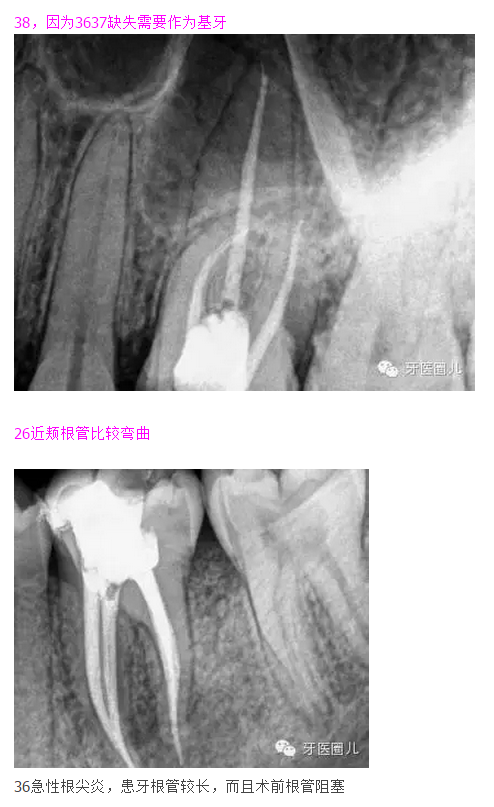

38,因?yàn)?637缺失需要作為基牙

這三個(gè)病例采用protaper器械,最后一個(gè)病例有不足,遠(yuǎn)中舌根根尖2mm有一個(gè)嚴(yán)重的向上彎曲,預(yù)備和充填時(shí)沒有到達(dá),術(shù)前評(píng)估和術(shù)中評(píng)估時(shí)覺得這個(gè)病例難度超過了我的操作范圍,但是患者沒有精力選擇更好的醫(yī)院,我于是和他講明狀況盡量做到我能做的了